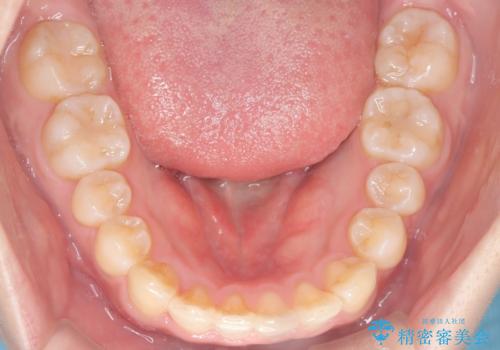

【ワイヤー矯正】前歯のがたがたをなおしたい

- 前歯のがたがたを主訴に来院されました。

叢生量も軽度なため短期間で治療を行っています。

治療中、装置の変更を希望されたため上下で装置が異なっています。